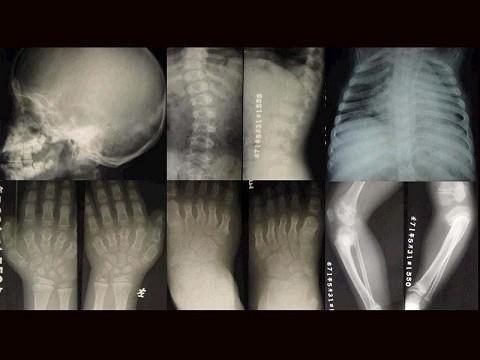

女,3岁,身体发育异常,如图所示,最可能的诊断为?(?)A.成骨不全B.粘多糖病C.软骨发育不全D.佝偻病E.侏儒症

问题 女,3岁,身体发育异常,如图所示,最可能的诊断为?(?)

选项 A.成骨不全 B.粘多糖病 C.软骨发育不全 D.佝偻病 E.侏儒症

答案 B